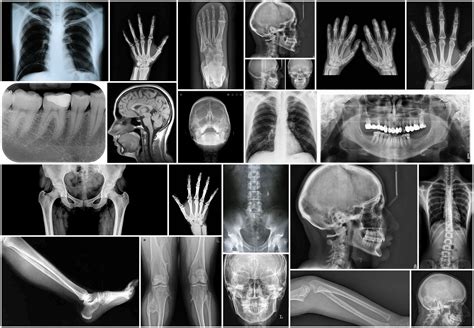

There are several types of Sex X Ray procedures, each tailored to specific diagnostic needs:

- Hysterosalpingography (HSG): This procedure involves injecting a contrast dye into the uterus and fallopian tubes to visualize their structure and detect any blockages or abnormalities.

- Vasography: This is used to examine the vas deferens in males, helping to diagnose issues related to infertility.

- Pelvic X-Ray: A general X-ray of the pelvic region that can help identify fractures, tumors, or other abnormalities in the bones and soft tissues.